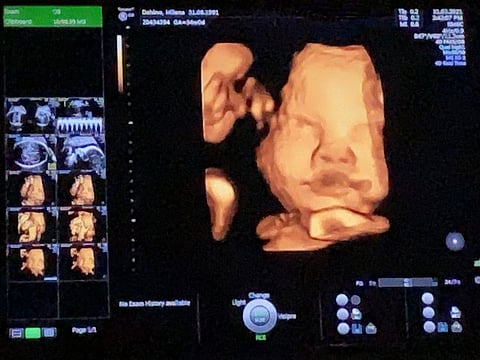

Getting a home ready for a baby is no easy feat – especially when you are dealing with a high-risk pregnancy. When Millena Kristie, a Filipino expat living in Dubai, found out she was pregnant, she waited anxiously for her second scan. “I forgot to ask the person scanning about the sex of the baby, so I asked my gynaecologist, who said it’s 90 per cent a girl. And then when I changed hospitals, the new gynaecologist, she said it’s definitely a girl,” she says.

When Kristie was at 36 weeks, she headed to the doctor for a scan. “My placenta was very low, by the end of it, I had high blood pressure, pre-eclampsia and cholestasis,” she recalls. While in this mode and trying to keep up her spirits, she and her husband joked with the doctor about the antics the child was pulling. “The foetal doctor was like, ‘she?’ and so she showed us the private parts and then she showed him while he was peeing – it was definitely a boy,” she laughs.